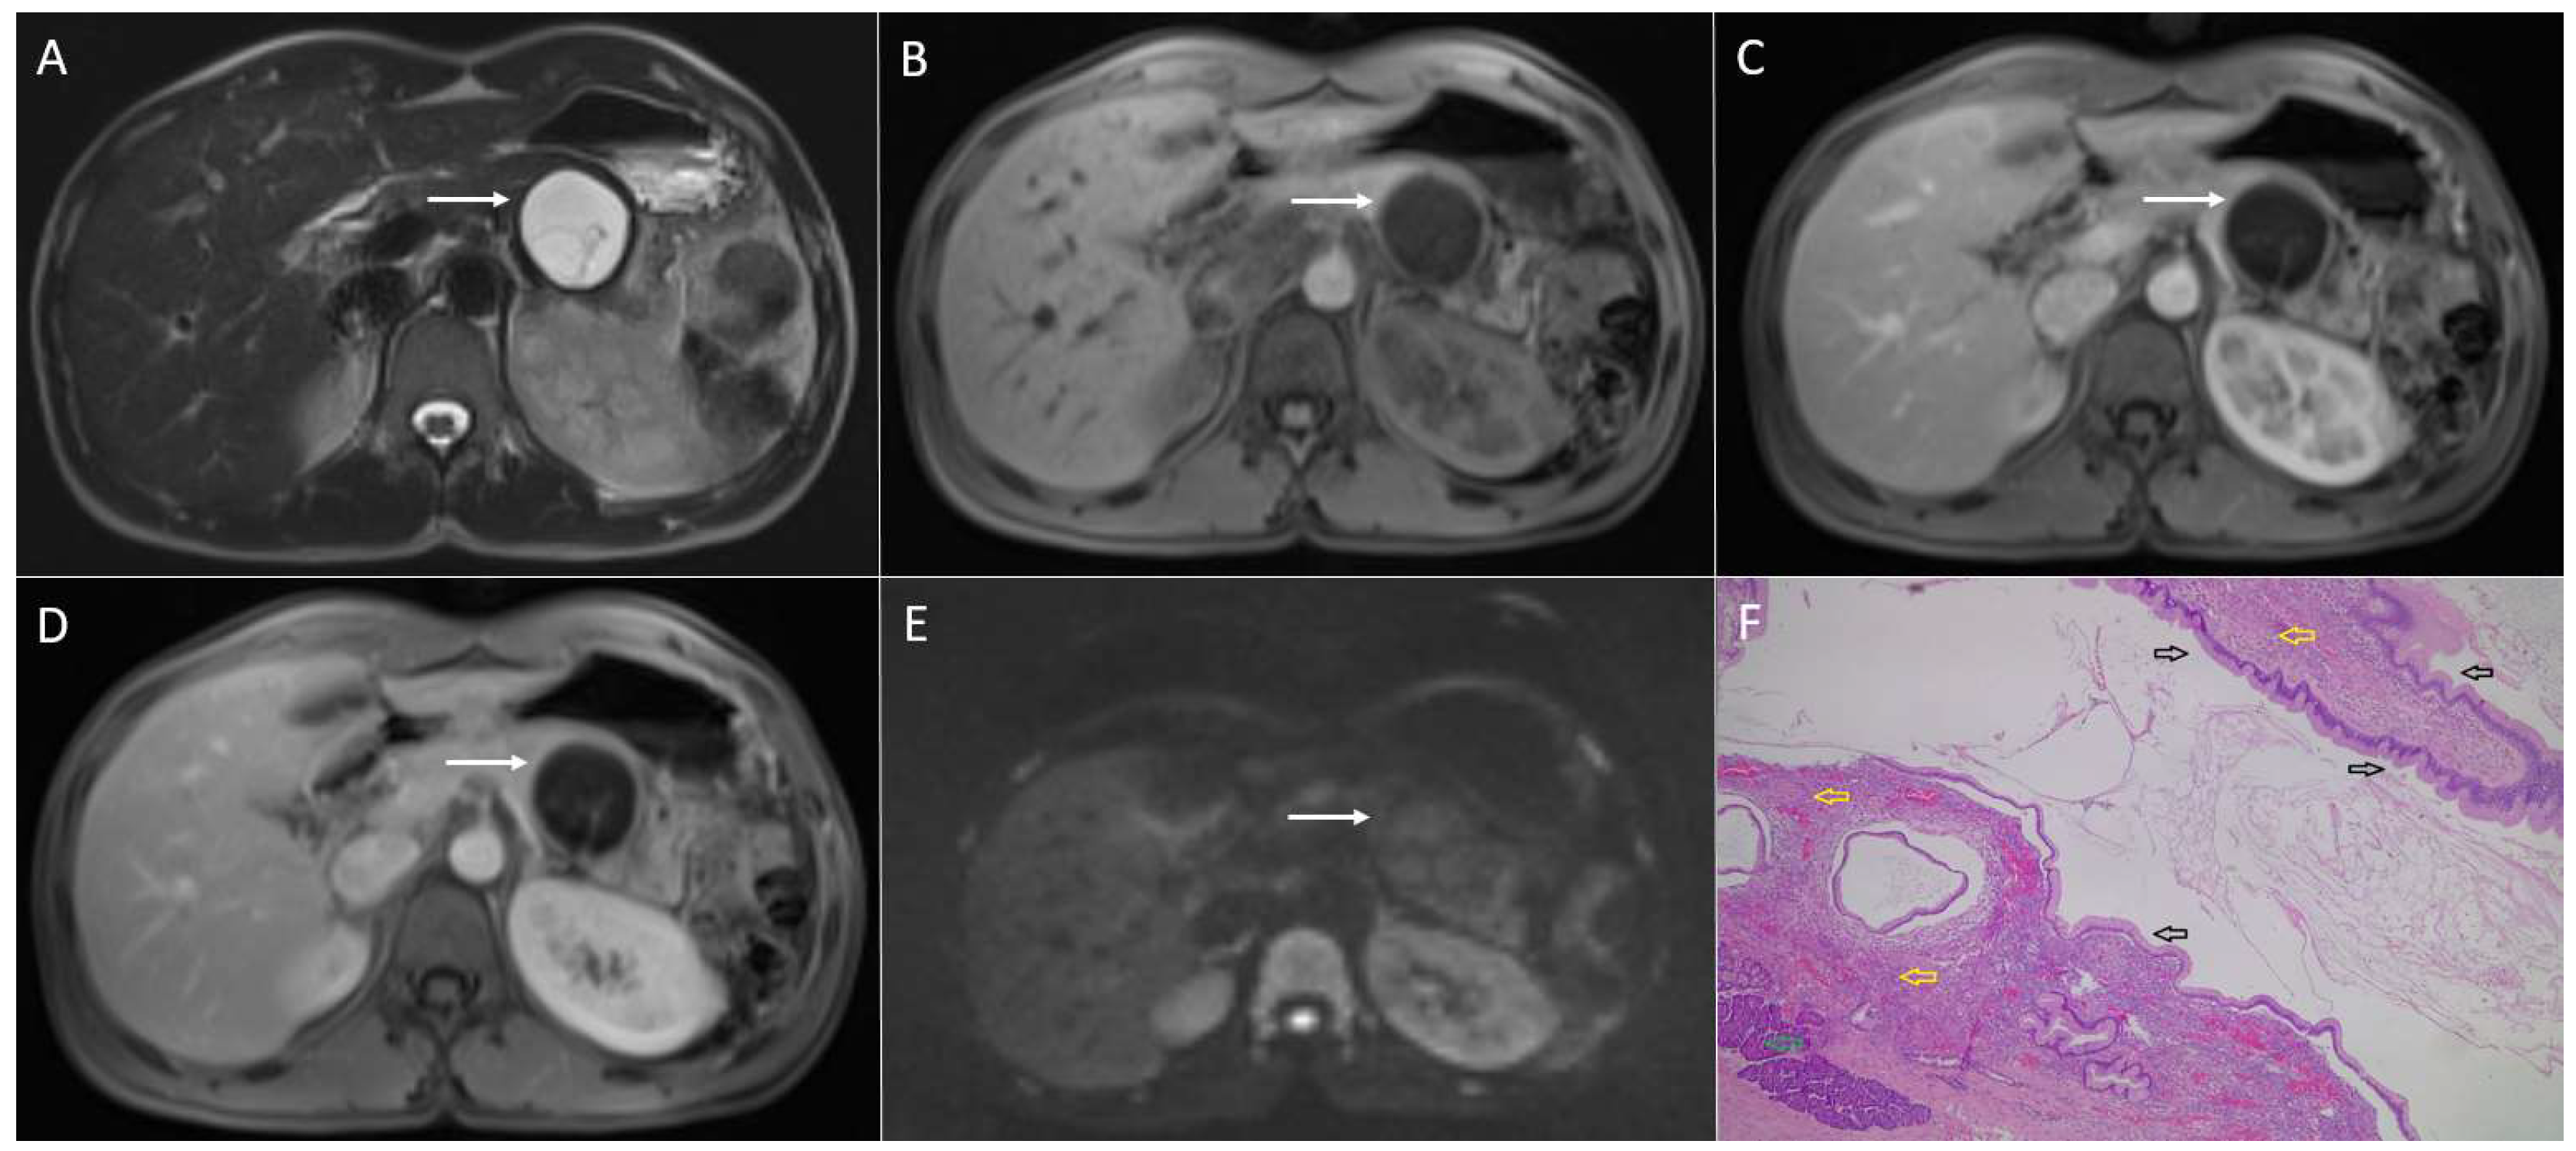

4.2. Mucinous Cystic Neoplasm